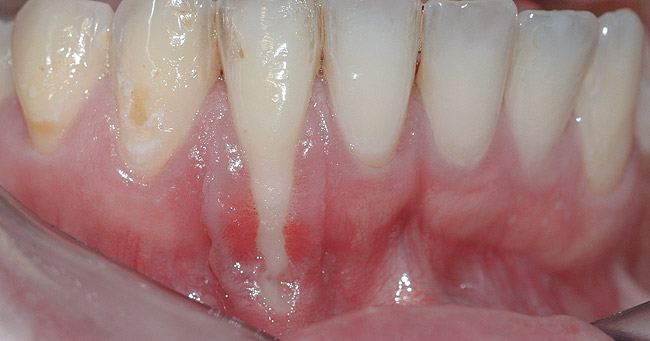

CASE 2 Fig 4. Post-orthodontic Miller Class II recession for which orthodontic treatment was not recommended. Clinical view 3 years after orthodontic treatment, showing relapse in teeth alignment and GR on lower left central incisor.

Figure 4